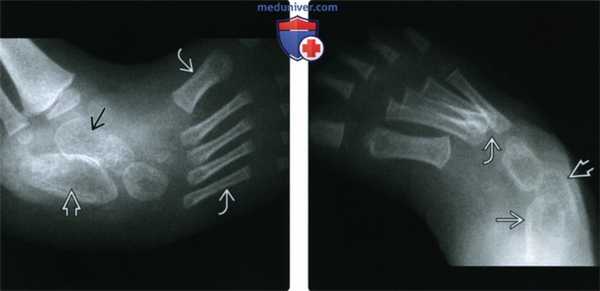

(Слева) Рентгенография в боковой проекции: определяется типичная для косолапости эквинусная деформация. Нагрузка на стопу симулирована; дальнейшее тыльное сгибание было невозможно. Величина угла между осью большеберцовой кости и линией, проходящей вдоль основания пяточной кости, составляет 90°, что указывает на эквинусную деформацию.

(Справа) Рентгенография лодыжки в косой ПЗ проекции у ребенка в возрасте пяти дней: визуализируется внутренняя ротация подошвенной поверхности стопы почти на 90° относительно длинной оси большеберцовой кости.

(Слева) Рентгенография стопы в боковой проекции со симуляцией нагрузки у маленького ребенка: определяется эквинусная деформация пяточной кости (избыточное подошвенное сгибание). Следует отметить, что таранная и пяточная кость расположены почти параллельно друг другу, что указывает на варусную деформацию заднего отдела стопы. Плюсневые кости расположены в ряд без перекрытия.

(Справа) Рентгенография в ПЗ проекции: подтверждается почти параллельное расположение таранной и пяточной костей (варусная деформация заднего отдела стопы). Плюсневые кош приведены, а их основания накладываются друг на друга больше, чем обычно (варусная деформация переднего отдела стопы в сочетании с супинацией).